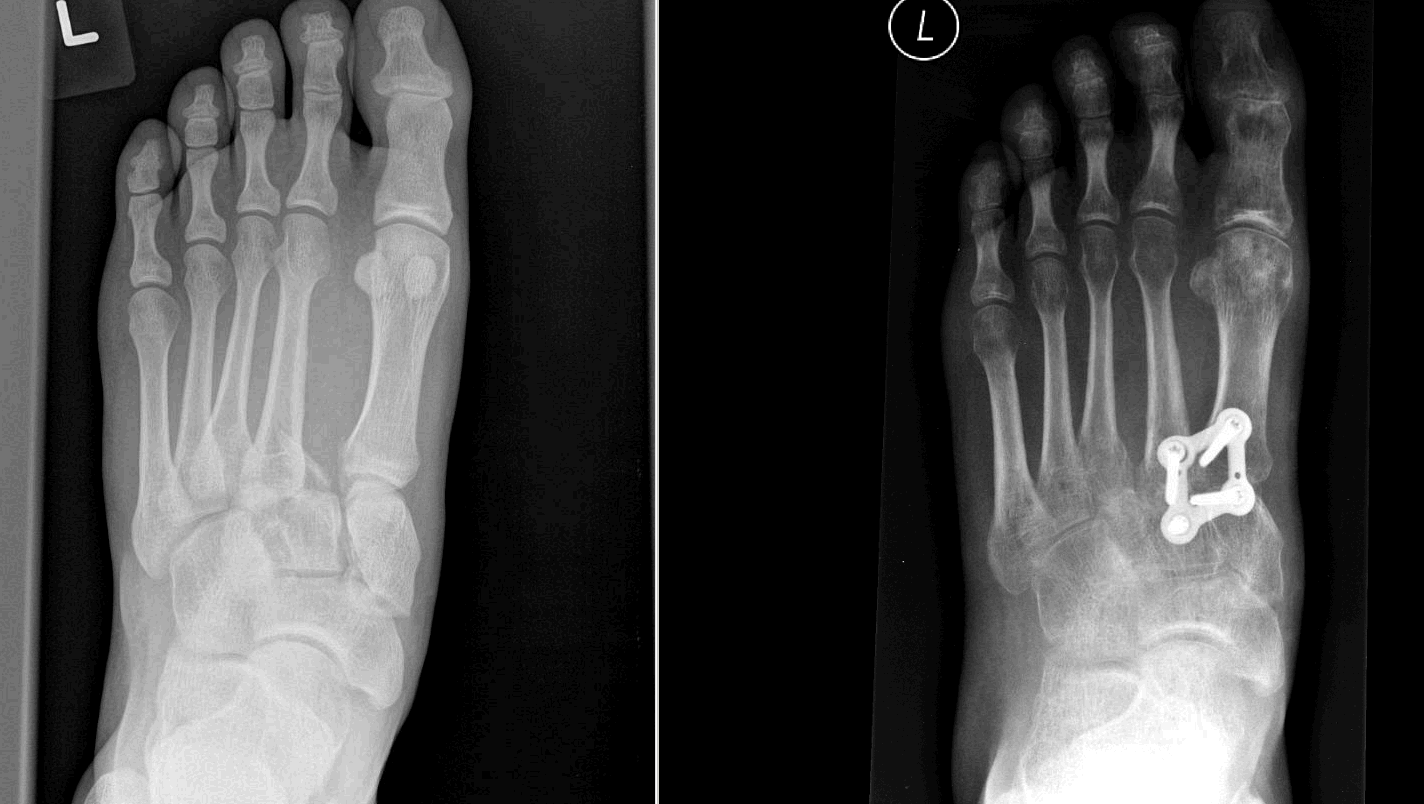

Lisfranc s fracture as seen on Xray